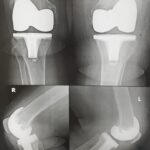

The surgery is performed under spinal or general anesthesia. Your surgeon will make an incision in the skin over the affected knee to expose the knee joint. Then the damaged portions of the femur bone are cut at appropriate angles using specialized jigs. The femoral component is attached to the end of the femur with or without bone cement. The surgeon then cuts or shaves the damaged area of the tibia (shinbone) and the cartilage. This removes the deformed part of the bone and any bony growths, as well as creates a smooth surface on which the implants can be attached. Next, the tibial component is secured to the end of the bone with bone cement or screws. Your surgeon will place a plastic piece called an articular surface between the implants to provide a smooth gliding surface for movement. This plastic insert will support the body’s weight and allow the femur to move over the tibia, similar to the original meniscus cartilage. The femur and the tibia with the new components are then put together to form the new knee joint. To make sure the patella (knee cap) glides smoothly over the new artificial knee, its rear surface is also prepared to receive a plastic component. With all the new components in place, the knee joint is tested through its range of motion. The entire joint is then irrigated and cleaned with a sterile solution. The incision is carefully closed, drains are inserted and a sterile dressing is placed over the incision.